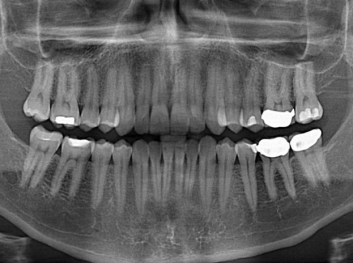

損壞的牙齒如何自我修復(fù)?近日,來自哈佛大學(xué)和諾丁漢大學(xué)的研究人員研發(fā)了能夠刺激牙齒干細(xì)胞再生的新型生物材料,而這種新材料研發(fā)成功的背后,正源于他們對(duì)牙齒如何實(shí)現(xiàn)自我修復(fù)這個(gè)課題的不斷探索。

據(jù)美國(guó)期刊《大眾科學(xué)(Popular Science)》報(bào)道,此種新型生物材料,不僅可以有效地取代傳統(tǒng)補(bǔ)牙填充物,刺激牙齒干細(xì)胞再生,患者也有望無需再接受根管治療,使蛀牙患者免除牙根感染或牙髓壞死的苦惱,一個(gè)全新的牙齒治療時(shí)代即將來臨。

Adam Celiz,是來自諾丁漢大學(xué)的研究人員,他和同事開發(fā)的這種新型合成生物材料,能刺激干細(xì)胞在牙髓部的生長(zhǎng)。與普通材料一樣,這種合成材料被填充到牙齒并用UV光硬化。

在體外測(cè)試中,材料刺激干細(xì)胞進(jìn)入牙本質(zhì)的增殖和分化速度,促進(jìn)形成牙齒骨組織。研究人員認(rèn)為,一旦材料在受損牙齒中應(yīng)用,這些干細(xì)胞可以自動(dòng)修復(fù)來自填充物上的損壞。在本質(zhì)上,該生物材料將使牙齒自愈。

在未來,Adam Celiz說,可再生材料能制成各種填充物以便受損牙齒的自身治愈,降低補(bǔ)牙失敗率,甚至?xí)蟛糠秩藢?duì)根管治療的需要。